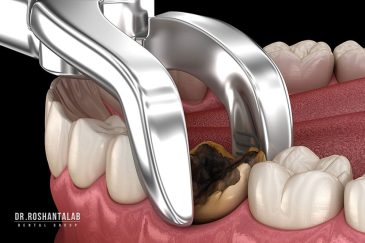

از عصب کشی و درمان ریشه دندان گرفته تا جراحی لثه و کشیدن دندان، تمامی مراحل توسط متخصص ترمیم دندان مدیریت میشود. ارائه باکیفیتترین خدمات ترمیم دندان برای سلامتی شماست.کاشت ایمپلنت فوری دندان